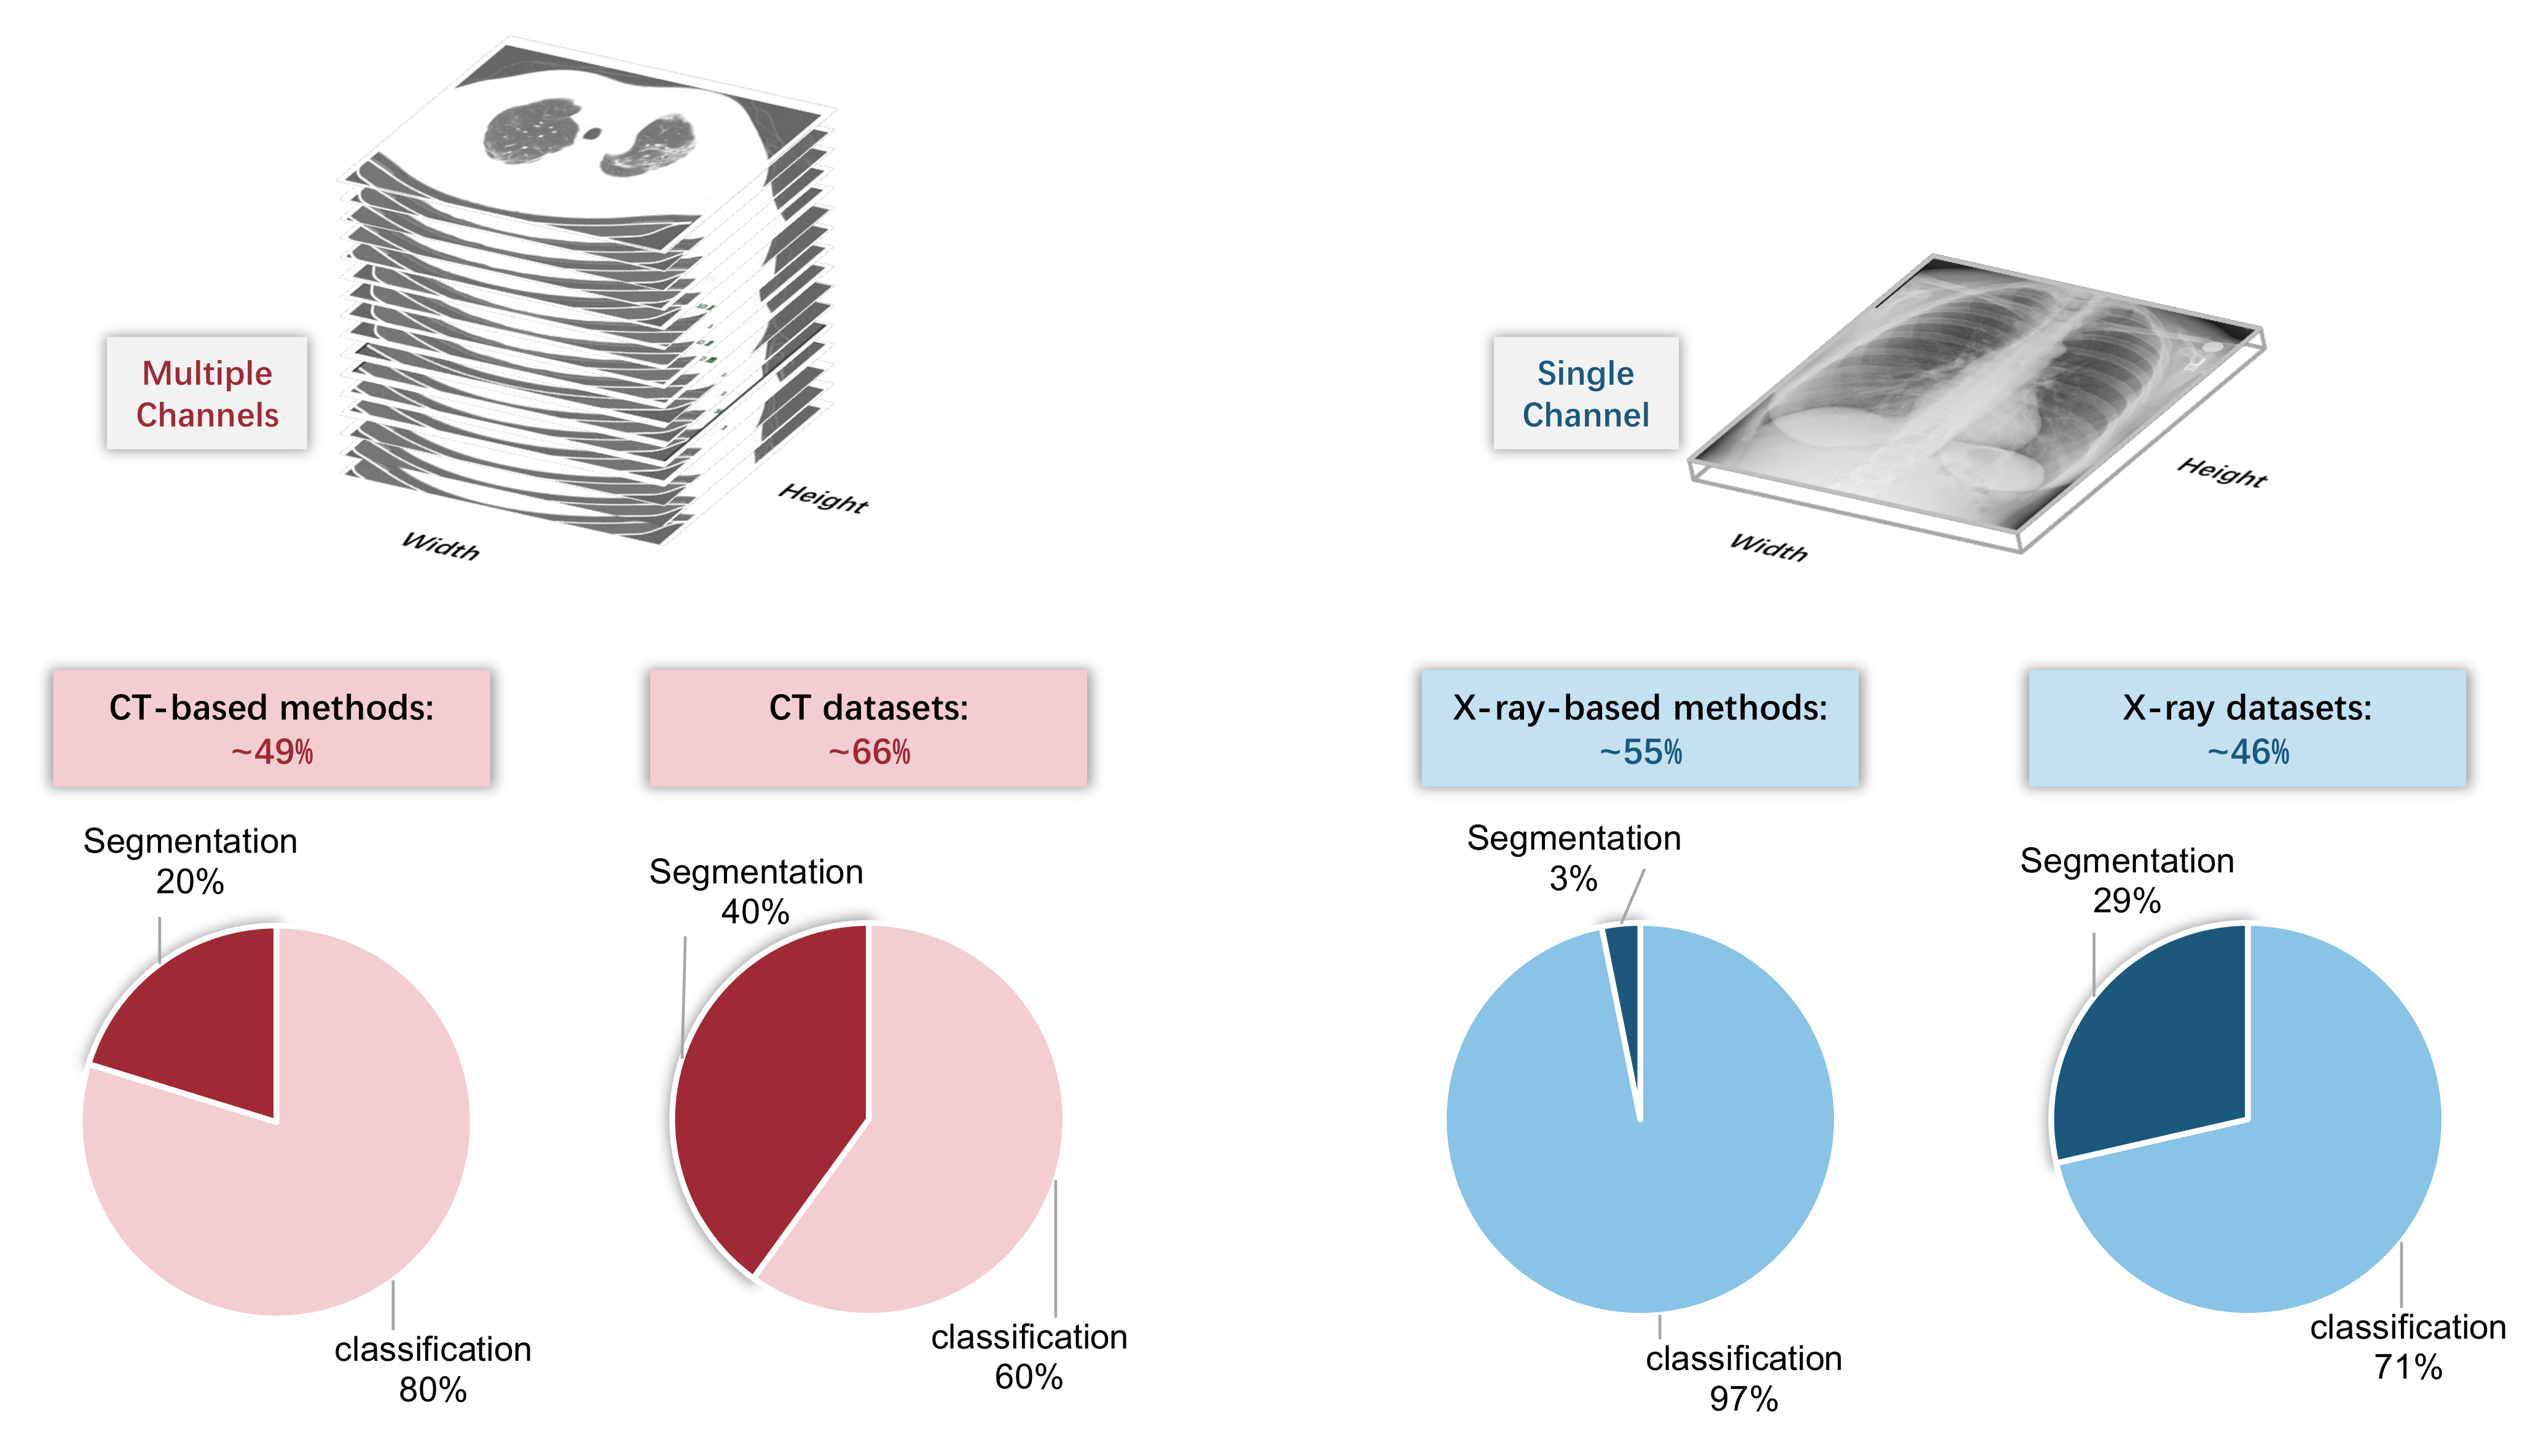

2. Input Modalities: CT or X-ray

2.2. Artificial Intelligence Perspective

3.1. Image-Level Diagnosis: Classification-Based Models

3.1.1. Overview

3.2. Pixel-Level Diagnosis: Segmentation-Based Models

3.2.1. Overview